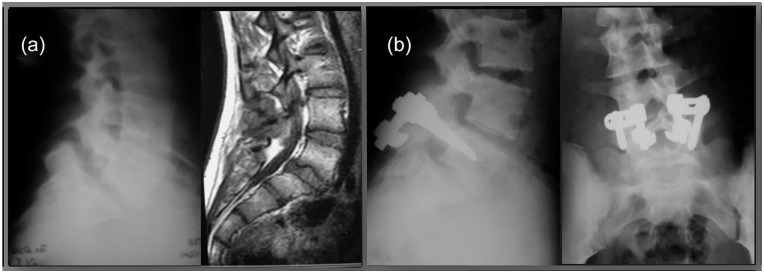

Abstract Image